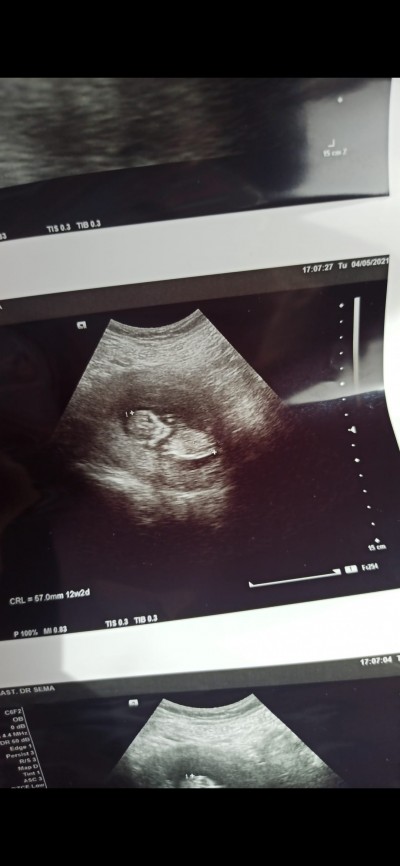

Cinsiyet hakkinda

Cinsiyet tahmini edermisiniz

Gebelik haftası

12